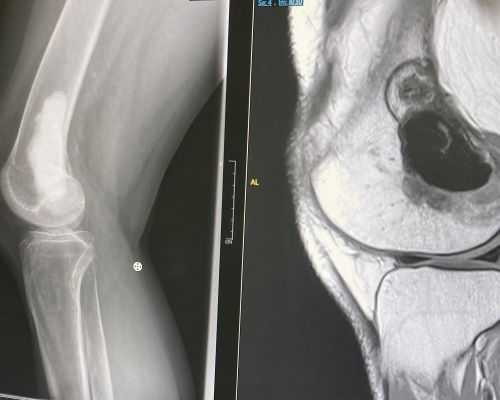

Sarah Brain – Giant Cell Tumour Right Distal Femur

Sarah, long term oncology patient and keen ROC advocate, kindly shared her story and experience at The Royal Orthopaedic Hospital.